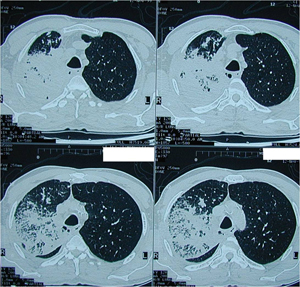

Εικόνα 3α-ζ

Διεγχειρητικές φωτογραφίες μετά από δεξιά άνω λοβεκτομή, δίκην περιχειρίδος (sleeve lobectomy).

Διακρίνεται το έλλειμμα στην συνέχεια του τραχειοβρογχικού δένδρου. Δηλαδή φαίνεται το περιφερικό άκρο του δεξιού κυρίου βρόγχου και το κεντρικό άκρο του διάμεσου βρόγχου. Προοδευτική συμπλησίαση των δύο άκρων και τελικο-τελική αποκατάσταση με συνεχή συρραφή, χρησιμοποιώντας μη απορροφήσιμο ράμμα

(Ράμμα Prolene Νο 3/0) και σε ένα στρώμα. Έκπτυξη του μέσου και του κάτω λοβού.